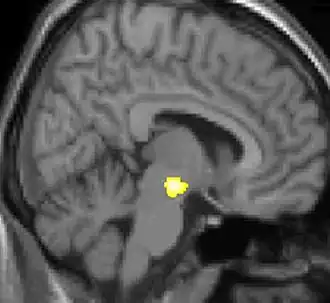

Um Unterschiede im menschlichen Gehirn zu analysieren, wird bei der Voxel-basierten Morphometrie das gesamte Hirnvolumen auf der Voxel-Ebene auf Anteile von grauer oder weißer Substanz oder von Gehirnflüssigkeit/Knochenstrukturen überprüft. Dabei werden alle kernspintomographischen Bilder der untersuchten Gehirne auf ein einheitliches Maß gebracht, um die Daten in einem standardisierten Raum auszuwerten. Dadurch sind Vergleiche zwischen mehreren Personen möglich. Zuerst werden die Ausrichtung und die Größe der Abbildungen der Gehirne korrigiert: Die Ausrichtung im Raum erfolgt durch Verschiebung und Drehung und die Größenänderung durch Skalierung und Scherung. Danach befinden sich alle Hirnvolumina im selben standardisierten Raum, die lokalen strukturellen Differenzen werden hervorgehoben. Die anschließende Unterteilung in Abschnitte ergibt parametrische Karten, mit korrespondierenden Anteilen für graue oder weiße Substanz, bzw. der Gehirnflüssigkeit/ Knochenstrukturen. Die Karten werden in jedem Voxel statistisch analysiert. So lassen sich die lokalen strukturellen Unterschiede errechnen, welche eine andere Konzentration oder ein unterschiedliches Volumen aufweisen[2].